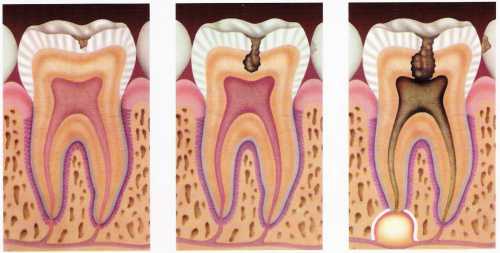

TRATAMENTO DE CANAL

O tratamento do canal da raiz dentária consiste na retirada da polpa (nervo) do dente, que é um tecido encontrado em sua parte interna. Quando a polpa inflama, como em casos de cáries muito grandes, o dente dói e o rosto pode ficar inchado.

O tratamento de canal é feito em várias etapas, realizadas em uma ou mais consultas.

Primeiramente é feita uma abertura na parte posterior de um dente frontal ou na coroa de um dente posterior. Em seguida a polpa infeccionada ou morta é removida. É determinado o comprimento do canal da raiz. O espaço pulpar e os canais são esvaziados e alargados, em preparação para o seu preenchimento. Um material em forma de cone é inserido em cada um dos canais e selado com um cimento apropriado. Se mais de uma visita for necessária, uma restauração temporária é colocada na abertura da coroa, a fim de proteger o dente no intervalo das visitas.